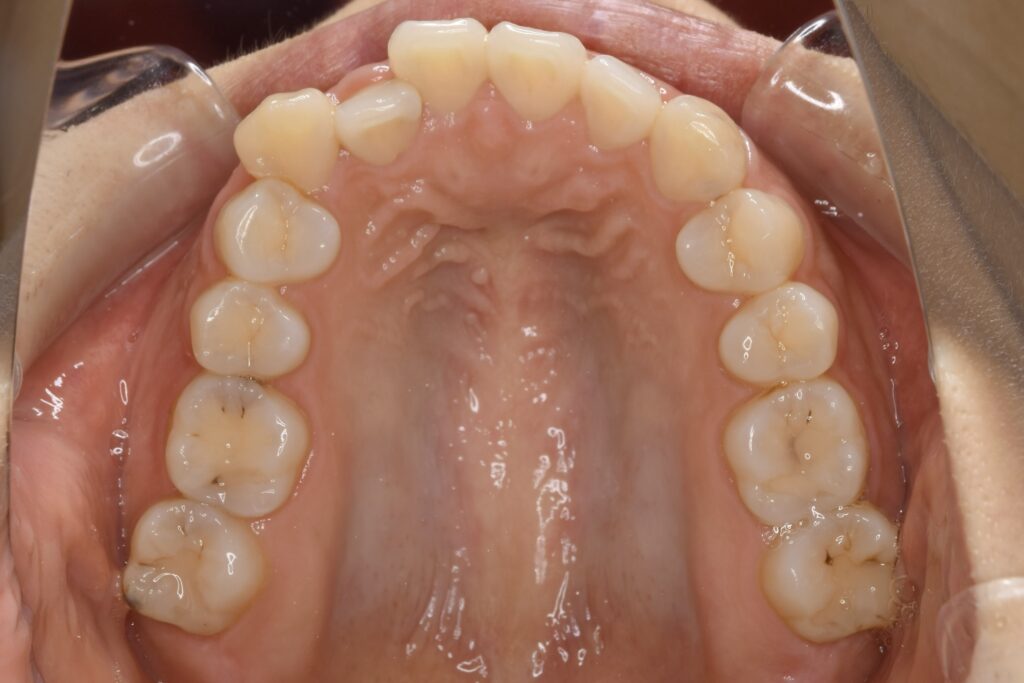

32歳 女性 治療期間:1年7ヶ月

AFTER

診断名・主な症状 叢生を伴う上顎前突

治療内容 上下とも歯を2本抜いて、上の前歯を後方に引きながら、でこぼこを治しました。

使用装置 マウスピース矯正装置(インビザライン)

治療期間 1年7ヶ月

通院回数 13回

費用 91万円程度(税別)   270